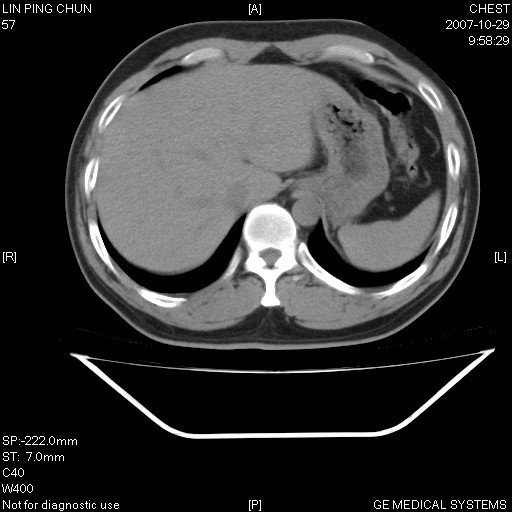

标题: CT10239:男,42Y.我自己的胸部CT扫描,今天10点突然咯血一次。

我自己胸部ct扫描,求助大家,我自己还不能给自己诊断。其他层面纵隔窗无异常。

补充:男,42y.今天10点突然咯血一次。余无异常。

左肺下叶后基底段小片结节状影,内部似见同心圆状分布条絮状影,整个病灶,质不实.局部见增粗血管影.

考虑;球形肺炎可能大.自已的身体如此重要,不进一步局部薄层及hrct?

左下肺后基底段磨玻璃样影,很多病都可以。不能吊以轻心。应该做局部增强hrct进一步检查,并严格抗炎治疗后复查或经皮活检。

左下肺后基底段小斑片泪膜玻璃样影,其内可见空泡影,边缘可见小毛刺影。建议抗炎治疗复查,肿瘤待排